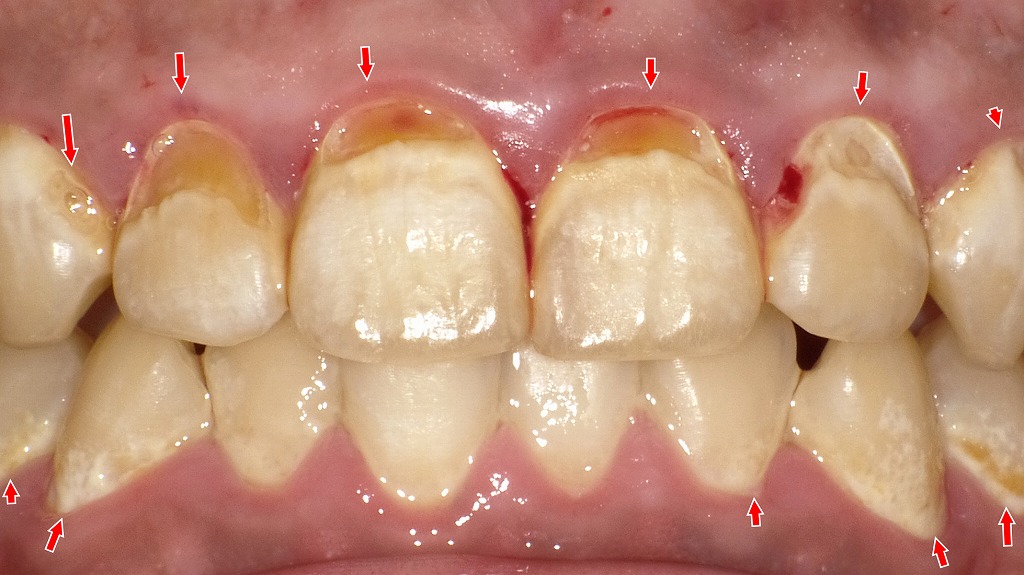

赤い矢印で示す部位は、前歯を中心に広がる初期〜進行した虫歯と歯肉炎の所見です。甘い清涼飲料水やスポーツドリンクを頻繁に摂取する「ペットボトル症候群」では、口腔内が長時間酸性環境となり、歯の表面が脱灰されやすくなります。その結果、歯の根元(歯頸部)や歯と歯の境目に虫歯が多発しやすく、同時に歯肉の炎症も起こりやすくなります。飲み物の種類や飲み方を見直すことが、虫歯予防の重要なポイントです。

この写真には、砂糖入り飲料を日常的に摂ることで起こる典型的な口腔リスクが複数確認できます。

◆ ① プラーク(細菌の塊)が歯面にべったり付着

赤矢印の部分には、白っぽく膜のように見えるプラークが残っています。

清涼飲料水を頻繁に口にすると、口腔内は長時間「糖+酸」にさらされ、プラーク内の細菌活動が活発になり、

- 酸産生の増加

- 歯の脱灰(溶ける)

- 歯肉の炎症悪化

が起こりやすくなります。

◆ ② 歯肉炎〜歯周病のサイン

歯ぐきは赤みを帯び、丸く腫れています。

これはプラークに含まれる細菌により引き起こされる歯肉炎で、放置すると歯周病へ進行します。

ペットボトル症候群の人は、飲み物を頻繁に摂る分だけ、清掃が不十分になりやすく、歯茎の炎症が慢性化します。

◆ ③ 酸に弱くなった歯面に虫歯リスク

矢印で示した前歯表面には、

白濁(脱灰)や褐色の虫歯初期病変が見られます。

ペットボトル症候群では、

- 飲料の糖による酸産生

- 飲料そのものの酸性

- 飲み続けることで口内が常に酸性に傾く

という「二重の酸ストレス」により、虫歯が急速に進行しやすい状態になります。

細かいスナックや清涼飲料を常飲する人に典型的な所見です。

◆ ④ 歯肉近くの歯面の荒れ(酸蝕・歯磨き過多含む)

前歯歯肉付近に見られる茶色い変色や表面のざらつきは、

酸蝕症+プラークの褐色着色が混在している可能性が高い所見です。

清涼飲料水に含まれるクエン酸や炭酸によってエナメル質が軟化すると、ブラッシングによる摩耗も受けやすくなります。